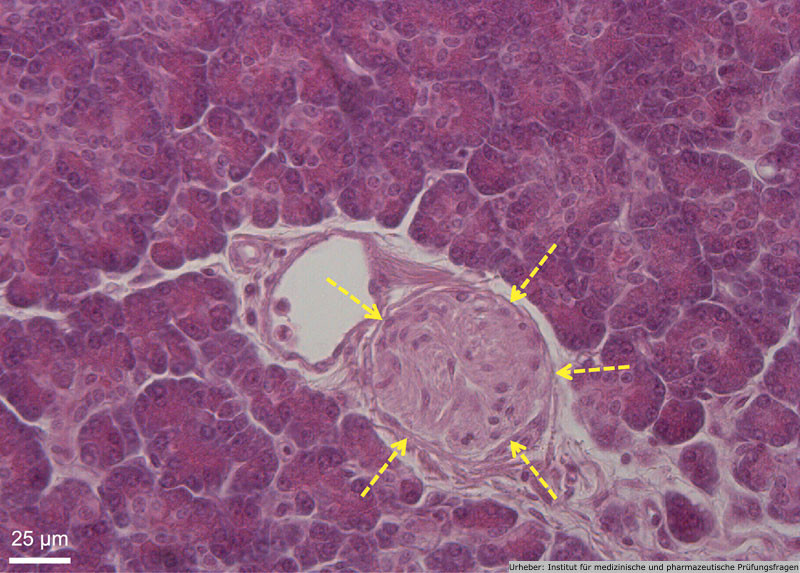

2.35 Das Präparat stellt einen histologischen Schnitt in Hämatoxylin-Eosin-Färbung dar.

Worauf weisen die Pfeile in der Abbildung hin?

- (A) einen Nerven

- (B) eine Langerhans-Insel

- (C) ein Epithelkörperchen

- (D) ein Haarfollikel

- (E) ein Meissner-Tastkörperchen